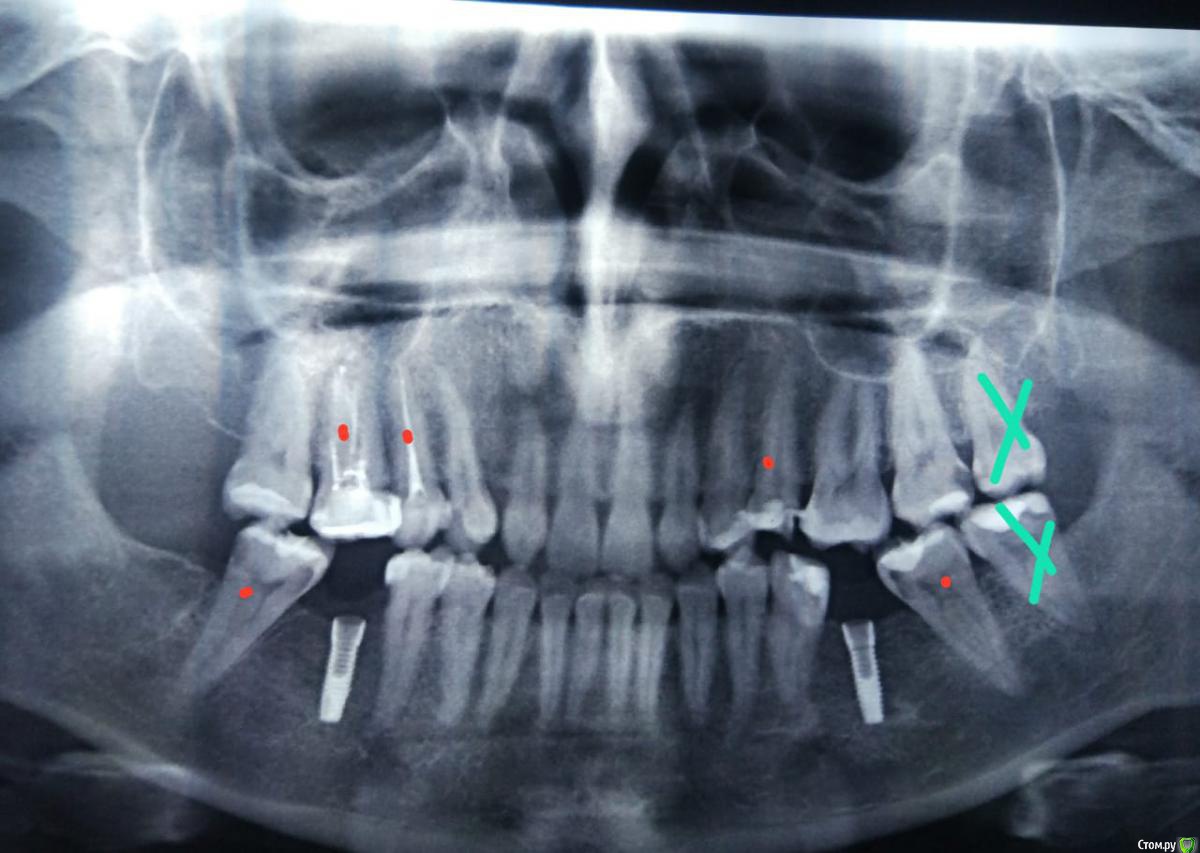

Яна88 Опубликовано 27 июня, 2020 Автор Поделиться Опубликовано 27 июня, 2020 (изменено) Приклепляю снимокКрасные точки- это где будут вкладкиДвух 8рок зачеркнутых нетСнимку 3 месяца Изменено 27 июня, 2020 пользователем Яна88 Ссылка на комментарий

krokomot Опубликовано 28 июня, 2020 Поделиться Опубликовано 28 июня, 2020 Во-первых, нужно было сначала решать вопросы с положением зубов, а потом устанавливать имплантаты!, на предоставленном вами снимке видны деформации с наклоном и выдвижением зубов, а также видно что для 6-х зубов мало места, и это означает что имплантаты не в оптимальной позиции, но это, скорее всего, поправимо. Так же, имеющиеся имплантаты и временные коронки на них, вы можете решить сразу проблемы с наклоном 7ых и выдвижением верхних шестерок, проведя, их интрузию, для этого не потребуется установка микровинтов. Можно вполне использовать опору коронки(временной) на имплантате для закрытия всех этих проблем. Ссылка на комментарий